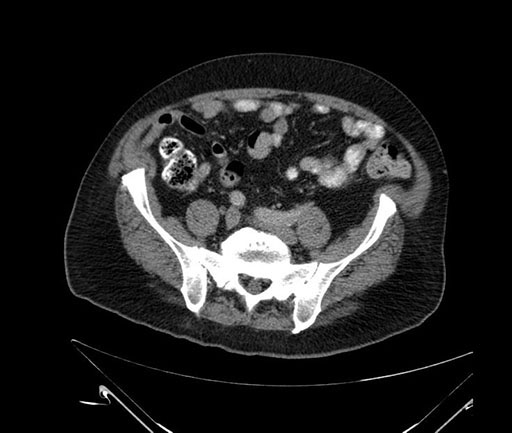

Whipple (pancreaticoduodenectomy) [case 7]

Imaging Analysis

Look through the patient's CT scan to identify any areas of concern for the necessary procedure.

Axial - 3 months prior